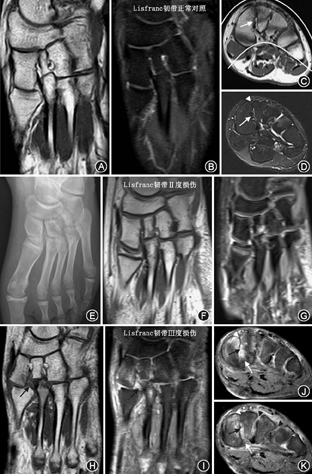

使用Siemens Magnetom Verio 3.0 T磁共振扫描仪,选择8通道膝关节Siemens knee coil线圈,扫描时足处于中立位,扫描视野(FOV)为22~25 cm,扫描层厚3 mm,扫描间隙0.3 mm,扫描序列包括足冠状位、横断位快速自旋回波法成像(turbo spin echo, TSE)-T1WI;重复时间(TR)450~750 ms,回波时间(TE)20~50 ms,足冠状位TSE-T2WI脂肪抑制序列(TR 2 700~5 000 ms,TE 50~100 ms),足矢状位TSE-PDWI脂肪抑制序列(TR 3 000~5 000 ms,TE 30~50 ms),足横断位TSE-T2WI脂肪抑制序列(TR 3 000~5 000 ms,TE 50~100 ms)。

MR检查者23例,MR图像上可清晰观察Lisfranc复合体韧带,包括C1(第1楔骨)与M2(第2跖骨)间韧带(经典Lisfranc韧带)及其他跖骨间韧带。冠状位T1WI、T2WI脂肪抑制序列显示Lisfranc韧带骨间束全长最佳,2例表现为Ⅰ度损伤,表现为信号异常但无断裂;12例Ⅱ度损伤,即为韧带部分撕裂;9例为韧带完全撕裂,表现为:(1)韧带信号的中断、或韧带信号的消失,(2)韧带周围水肿,或正常韧带信号区域被水肿区域取代(图5I)。横断位T1WI和T2WI脂肪抑制序列显示经典Lisfranc韧带三束,背侧束损伤者15例,骨间束损伤者23例,跖侧束损伤者12例,三束共同损伤者7例,背侧+骨间束损伤者15例,跖侧+骨间束损伤者11例。合并跖骨间其他韧带损伤者11例,均伴有M2~M3跖骨间韧带损伤(图5J、图5K)。T1WI横断位可清晰观察中足足弓,正常中足横弓呈"拱桥样"结构,6例表现为"拱桥样"结构消失,中足横弓塌陷。T2图像上跖骨基底部骨折主要表现为骨髓水肿及周围软组织肿胀,此征象导致骨折线不清晰及周围骨片显示不清,T1WI更有助于显示骨折线,但骨折线及碎骨片的显示明显不如CT三维成像。8例儿童和青少年患者,4例Lisfranc关节损伤通过MR诊断,儿童足部MR上可检查X线及CT上不可见的隐匿性骨折,主要表现为M1和M2、C1和C2骨髓水肿,Lisfranc韧带损伤征象同成人相似(图5E,图5F,图5G)。

MR以其对软组织显像优势以及多层面显像优势,可检测出X射线与CT上不可见的Lisfranc韧带损伤。在本研究中23例MR检查者均伴有骨间束损伤,而不像Nunley等[4]描述的先累及背侧束和背侧关节囊,随着损伤的加重,再累及骨间束,最后累及跖侧束。本研究发现11例患者在无背侧束损伤的情况下,出现骨间束+跖侧束的损伤。除C1~M2间韧带损伤,Lisfranc关节损伤可伴有M2~M5跖骨间韧带损伤,其中伴M2~M3韧带损伤占47.8%(11/23)。

儿童Lisfranc关节损伤又称为"Bunk Bed"损伤(双层床骨折)[2],Jonhson[2]研究表明该病好发于3~6岁儿童群体,其描述的16例患者中,全部伴有M1基底部骨折,仅有1例合并M2基底部骨折,并指出M1损伤可合并Lisfranc韧带损伤,Lisfranc韧带损伤常合并M2基底部的撕脱骨折,X线上Lisfranc关节损伤无脱位时容易漏诊,这时负重与非负重正位前后对照、双足对照有利于病变的检出,X线正位片上M1~2跖骨基底部间距增宽为该关节损伤的可靠征象,MR可检测出Lisfranc韧带的损伤及隐匿性骨折(图5E,图5F,图5G),M1基底部累及骺线导致愈合畸形,余骨基底部无骺线,则多见创伤性跖跗关节炎。